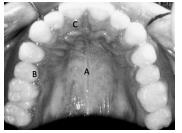

Considerando a imagem apresentada acima, julgue o item subsecutivo.

A imagem representa uma tomada intrabucal de um indivíduo com dentição mista.